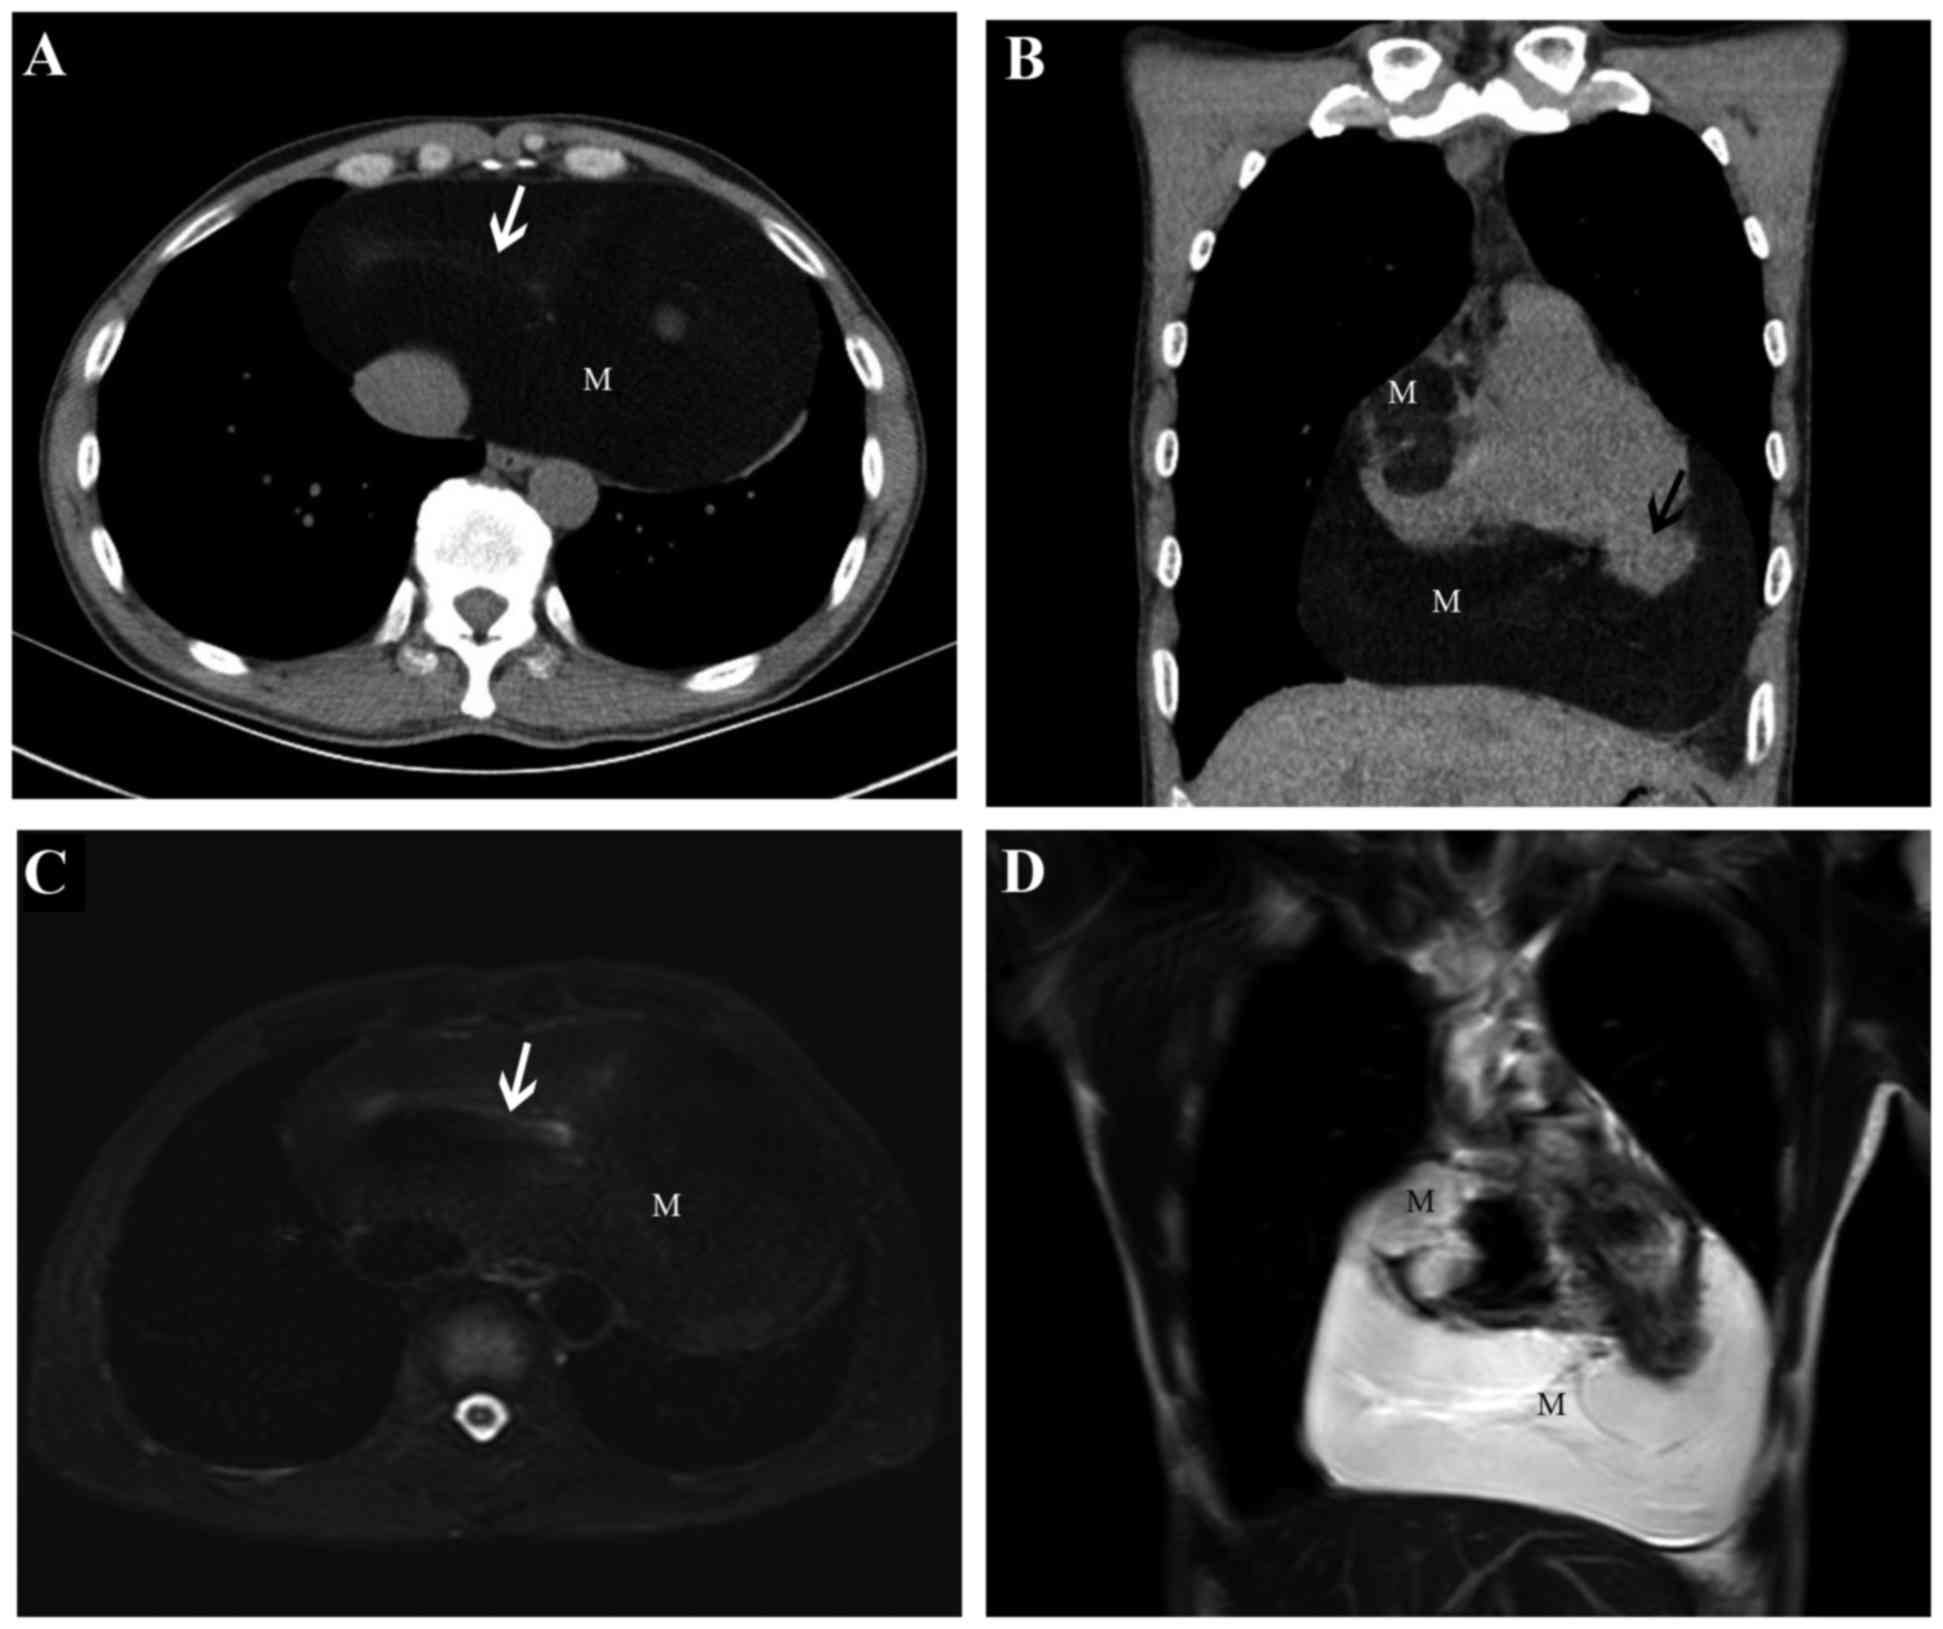

Preoperative images of computed tomography scan. Encapsulated lipoma …

Multiple well‑differentiated cardiac liposarcoma with a concomitant …

Pericardial Lipoma – Cardiac Case Studies – CTisus CT Scanning

Chest wall lipoma images, diagnosis, treatment options, answer review …